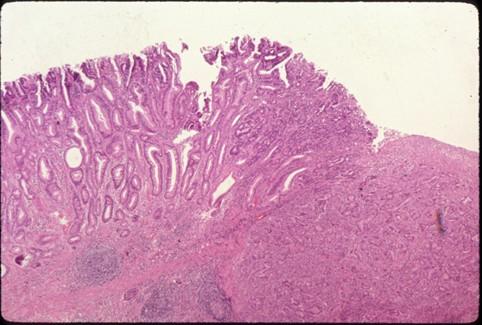

疾病(病理主体)的分类恶性上皮性肿瘤/腺癌

部位(按器官分)胃(部位)/前庭

检查方法病理切片(微观)

肿瘤的肉眼分类0型(表在型)/IIa型(IIa+IIc)

肿瘤最大直径30~34

肿瘤的深度sm